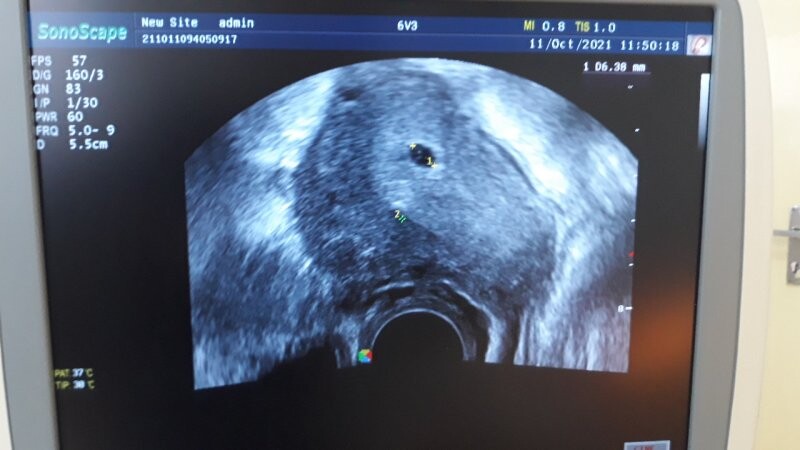

Dobrý den, chci se zeptat, co znamená dvojka na ultrazvuku viz foto. Děkuji

takto těžko hodnotit bez možnosti komplexního ultrazvukového vyšetření, nicméně to vypadá, že lékař jen omylem "odkliknul" další značku, která nic neznamená. Pro Váš klid se při další kontrole optejte, zda je vše v pořádku.